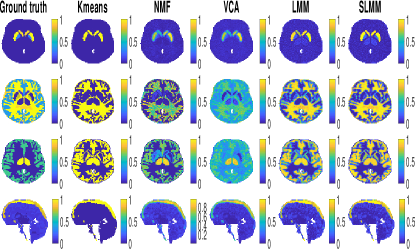

Figure 7 depicts the factor proportion maps estimated by the compared methods. The corresponding estimated factor TACs are shown in Fig. 8. The LMM and SLMM algorithms estimate four distinct TACs associated with different tissues, as expected. In the first row of Fig. 7, corresponding to SBF, all methods seem to correctly recover the main localization of the stroke area. However, the proposed SLMM approach identifies a significantly larger area. This result seems to be in better agreement with the stroke area identified in the MRI acquisition of the same patient (see st column of Fig. 9). Moreover, the specific gray matter factor proportion maps estimated by SLMM and K-means shows high values in the thalamus, which is a region known to present specific binding of [18F]DPA-714. Another remarkable result is the factor proportion maps for the blood. The sagittal view represented in the last row is in the exact center of the brain. Both NMF and SLMM recovers factor proportion maps that are in very good agreement with the superior sagittal sinus vein that passes on the higher part of the brain. On the contrary, VCA estimates two factors which seem to be mixtures of the vein TACs and other region TACs.

Fig. 9 depicts three different views of the AVC area identified by the expert on MRI acquisition (st column), the estimated specific gray matter factor proportions (nd-th columns) and the estimated corresponding variability (th column). This figure shows that SLMM provides sharper and more accurate maps, characterized by a larger area with high uptake, as in the MRI ground-truth. This figure also compares the map recovered by K-means, which is used as the initialization of the proposed SLMM, with the final SLMM estimate. It is possible to note an interesting improvement of the final estimate when compared to its initialization. This demonstrates that the method converges to an estimation of the specifically bound gray matter that is more accurate with the proposed model.